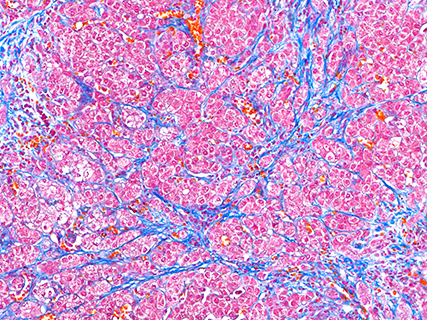

Azan染色(マウス肝臓)